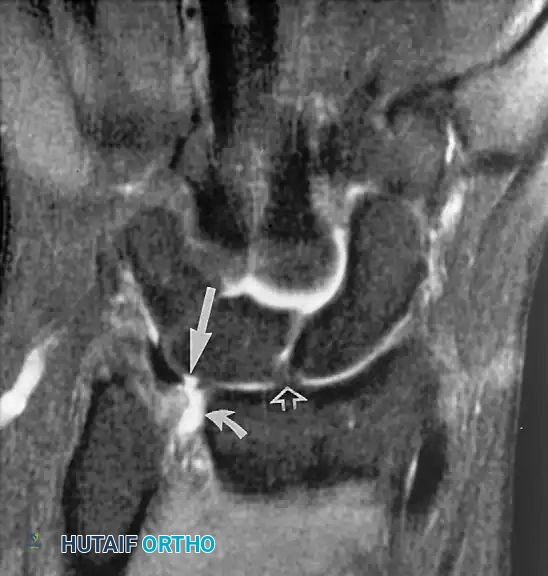

The Wrist: Carpal Ligaments and the TFCC

In the wrist, the most common indication for MRI is the evaluation of the intrinsic carpal ligaments and the triangular fibrocartilage complex (TFCC).

Triangular Fibrocartilage Complex (TFCC) Injuries

The TFCC is the primary stabilizer of the distal radioulnar joint (DRUJ) and acts as a shock absorber, transmitting approximately 20% of the axial load from the carpus to the ulna. It is composed of signal-poor fibrocartilage. Perforations or tears in the TFCC appear as linear defects or gaps filled with hyperintense fluid on coronal gradient-echo or T2-weighted pulse sequences.

Surgical intervention is indicated for Palmer Class 1B (ulnar avulsion) or 1D (radial avulsion) tears that fail conservative management, particularly when associated with DRUJ instability. Central perforations (Class 1A) are typically debrided rather than repaired due to the avascular nature of the central articular disc.